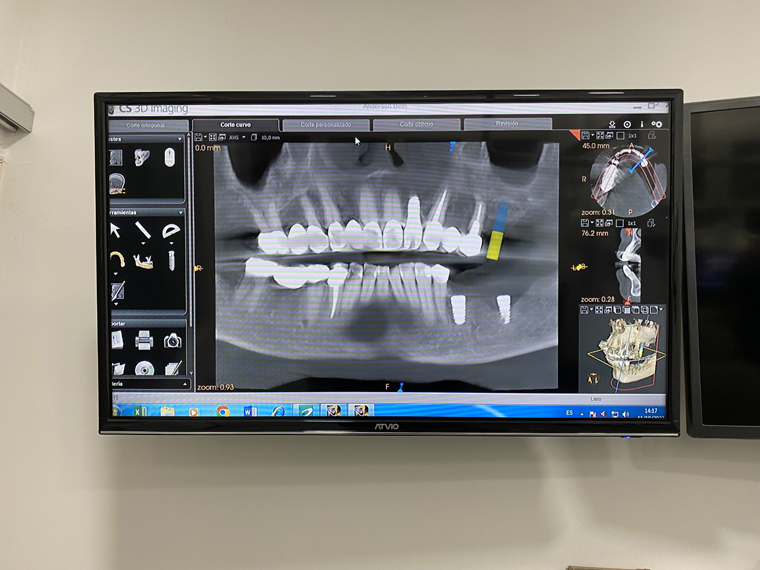

The process started with a 3D scan of her mouth to identify what actually needed to be done. The bone graft was then done followed by the placing of the titanium posts for the implants in her jaw. Great care is taken to make sure that her mouth healed correctly, including three days of infrared laser treatments after each post or graft as well as antibiotics. There is then a wait of several months as the posts set and the jaw heals. Once, her mouth was ready, the next stage involves taking detailed impressions of the mouth with a digital device and actual impressions with a mold. The data from these are used to make the actual teeth at the lab (my crowns and implants were made with the 3D cutter in his office). Finally, the day comes to actually install the implants and bridge. Despite, the length of the process, she was absolutely delighted with the quality of the process, treatment and the results at Dental Studio by Pedro Ortiz.